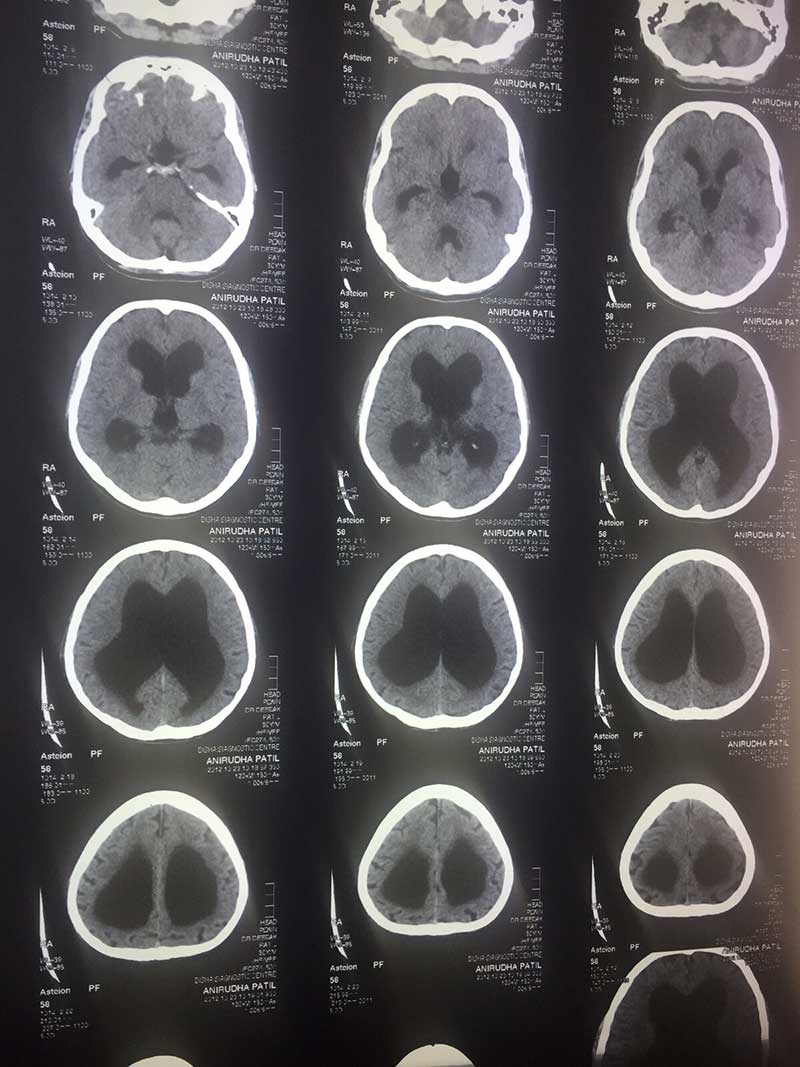

Preop Mri 1

PRE OP CT 2

PRE OP CT

Post Shunt with Cerebellar TB

Post Shunt